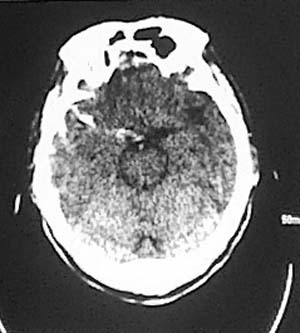

临床予以止血,降颅内压等处理治疗后5日,患者症状缓解,呕吐恶心症状明显减轻,仍然腰背部疼痛乏力。

复查ct:

支持蛛网膜下腔出血.右额叶脑挫伤

左额/顶部硬膜下积液,蛛血,右额叶病灶第一次有高密度影,应该是脑挫裂伤,外伤性脑梗塞应该在第一次照片上就出现.

支持蛛网膜下腔出血.右额叶脑挫伤,左额颞部硬膜下积液。

左侧额顶部硬膜下积液,右侧侧裂池内高密度影考虑蛛血,右额叶低密度影是由于脑挫裂伤还是外伤性脑梗塞不好说,但右枕部骨缝,边缘锐利,局部软组织未见异常,不考虑骨折,建议细致观察骨缝边缘有否硬化;考虑枕骨变异可能。